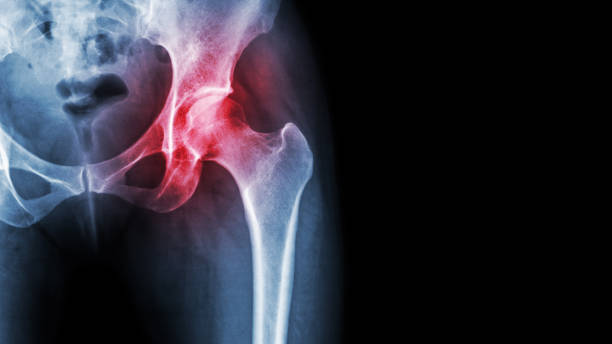

골반통증은 많은 사람들이 겪는 건강 문제 중 하나입니다. 장시간 앉아있거나 일을 많이 하다보면 골반 주변 근육이 약해지고 불균형해지는 경우가 많아 골반통증이 발생할 수 있습니다.

이런 골반통증의 경우 근육이 약해지거나 자세불량 등 다양한 이유가 있는데요.

이런 통증을 해결하기 위해서 스트레칭을 해주면 좋다고 합니다.